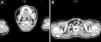

Saturation was maintained at approximately 99% with the oxygen cannula at 2L/min. Physical examination showed palpable subcutaneous emphysema involving the submandibular region, anterior and lateral aspect of the neck, as well as the bilateral supraclavicular regions. There were minor inflammatory signs but there was no local dental infection. Chest radiograph showed pneumomediastinum and subcutaneous emphysema in the neck region (Fig. 1). A computed tomography scan was performed that showed: emphysema extending from the mandibular region to the mediastinum (Fig. 2A and B), as well as the presence of pneumopericardium and left side pneumothorax (Fig. 3A and B) The laboratory tests showed slightly elevated white counts 12400/μL without shift-to-left. The band form was 4% and the segmented form was 80% of total leukocytes. C-reactive protein was 7.4mg/dL. After treatment with a second-generation cephalosporin administered intravenously along with oxygen and oral non-steroid anti-inflammatory drug, the fever subsided within 24h after admission and the symptoms resolved. The patient was discharged 4 days later. After discharge, the patient took oral first-generation cephalosporin for an additional five days. She had a complete clinical and radiological recovery without recurrence of disease (Fig. 4).